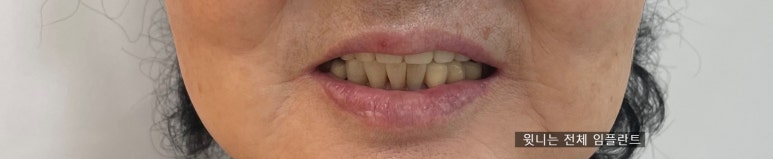

임플란트로 치료 후 사진 (윗니는 모두 전체임플란트)

위에 틀니를 끼고 있는데 불편해서 임플란트를 하고 싶어요

치료전: 위쪽 앞니 치아머리는 하나도 없는 상태

위쪽 앞니 치아머리는 하나도 없는 상태로 어금니 하나에 지탱하여 틀니를 착용하는 상태였으나

오래된 틀니가 너무 불편해서 고정된 임플란트를 원하고 계셨습니다.

임플란트 전후

보이는 윗니는 전체 임플란트인 상태

위 사진에서 보이는 윗니는 전체 임플란트인 상태로

자연스럽게 진행되었습니다.